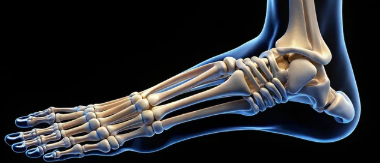

**골감소증(Osteopenia)**은 골밀도가 정상보다 낮지만, 골다공증(Osteoporosis)으로 진단될 정도로 심각하지 않은 상태를 의미한다. 골감소증을 방치하면 골다공증으로 진행될 가능성이 높으며, 뼈가 약해져 골절 위험이 증가할 수 있다. 이번 글에서는 골감소증의 증상, 주요 원인, 치료 방법 및 예방 전략을 5개 항목으로 상세히 정리해보겠다.